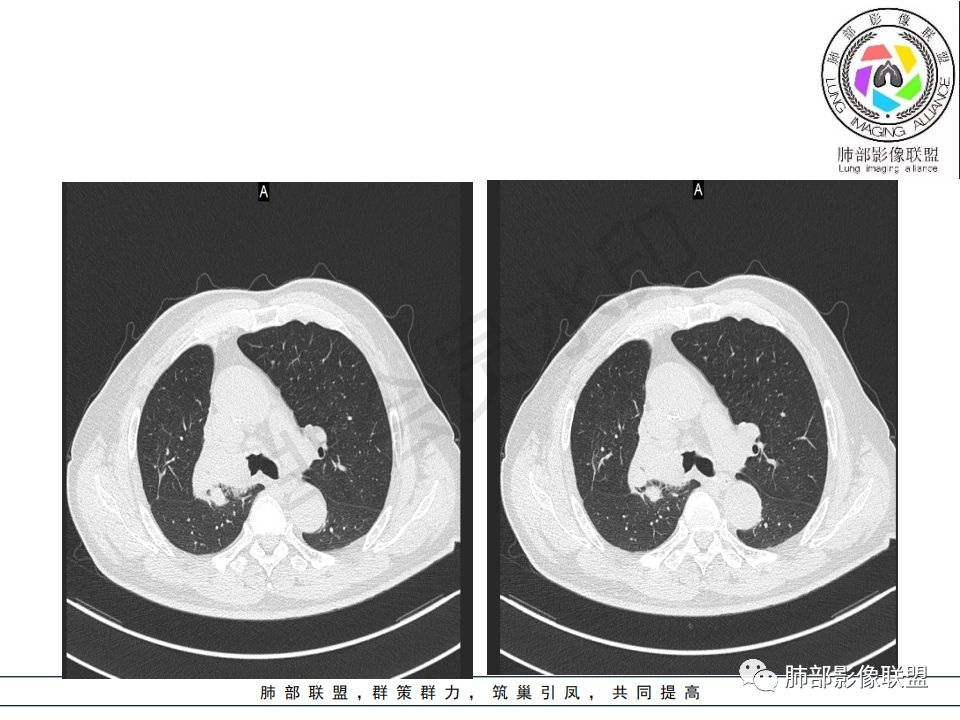

病史:男.77岁,咳嗽1月;干咳,少许白痰,无发热,2013胃癌术后,角蛋白24.65(0-3.07),SCC和proGRP不高;

影像:影像右侧大支气管阻塞,临床没有症状或很轻微,要想到胃腺癌转移;胸壁代偿好,透亮度稍低不明显,慢性过程;34.8-52.5HU,主病灶支气管前壁另有1结节,都做成增强两期了,动脉期较平扫有强化;

诊断:多发,转移,无淋巴结及胸腔积液;

鉴别:原发鳞癌。

晨读:患者老年男性,以咳嗽一月就诊,少量白痰,胸CT:纵隔右移,右肺体积缩小,气管下段管壁可见结节样改变,气管软骨变形,气管下段及右主支气管可见新生物向管壁浸润,并向管腔外生长,右上肺肺不张,但不张边缘可见病灶呈膨胀性生长,可见分叶,增强后强化明显。考虑:肺部恶性病变(鳞癌?)

右肺上叶肿块,边缘光滑,略膨隆,近段支气管堵塞,平扫密度均匀,增强后不均匀强化,其内可见不规则血管和坏死,纵隔淋巴结肿大,老年男性,无感染性病史,综合考虑恶性肿瘤(鳞癌,腺癌),鉴别:OP(一般下叶多见)

老年男性,右肺气管内软组织影,支气管变窄截断,右肺上叶阻塞性肺不张,内见细点状钙化,周围看见小结节,增强不均匀强化,考虑:原发肺恶性鳞癌。胃癌病史,转移不出外。鉴别神经内分泌癌,类癌。

晨读病例:老年男性,症状轻,右侧胸廓略塌陷,右肺主支气管内外软组织影,支气管变窄截断,右肺上叶不张,其内见细砂样钙化,周围看见小结节,右肺门看见一淋巴结稍大,增强不均匀强化,胃癌病史,常规考虑:转移,或原发肺恶性鳞癌。鉴别支气管TB?